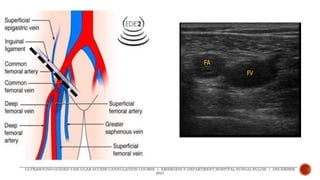

 Common femoral artery

 midpoint of inguinal

ligament

 Common femoral vein

 medial to common

femoral artery

 Common femoralartery  midpoint of inguinal ligament  Common femoral vein  medial to common femoral artery ULTRASOUND-GUIDED VASCULAR ACCESS CANNULATION COURSE | EMERGENCY DEPARTMENT HOSPITAL SUNGAI BULOH | DECEMBER 2021